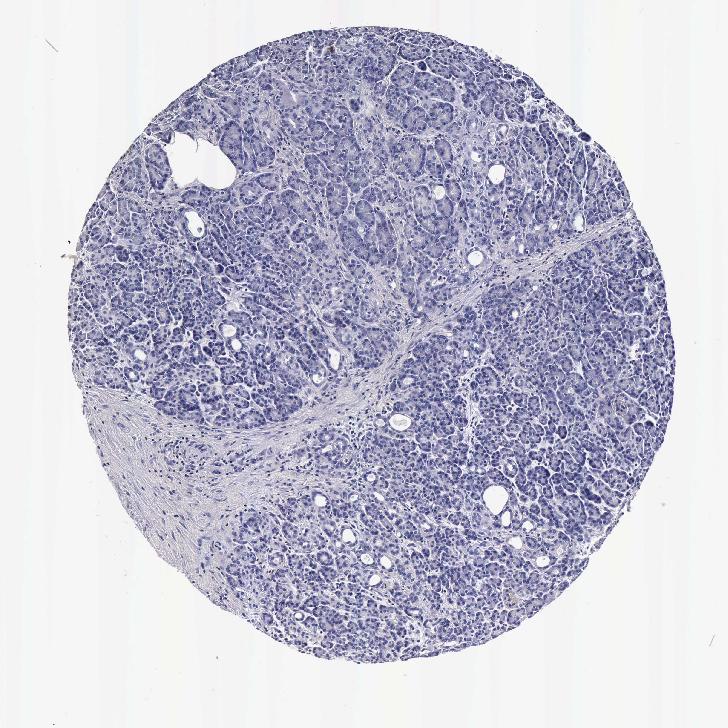

PANCREAS - Antibody stainingi

Antibody staining in the annotated cell types in the current human tissue is reported as not detected, low, medium, or high, based on conventional immunohistochemistry profiling in selected tissues. This score is based on the combination of the staining intensity and fraction of stained cells.

Each image is clickable and will lead to virtual microscopy that enables deeper exploration of all samples and also displays staining intensity scores, fraction scores and subcellular localization as well as patient and tissue information for each sample.

Antibody HPA053194Antibody CAB000352

Exocrine glandular cells Not detectedNot detected

Pancreatic endocrine cells HighHigh